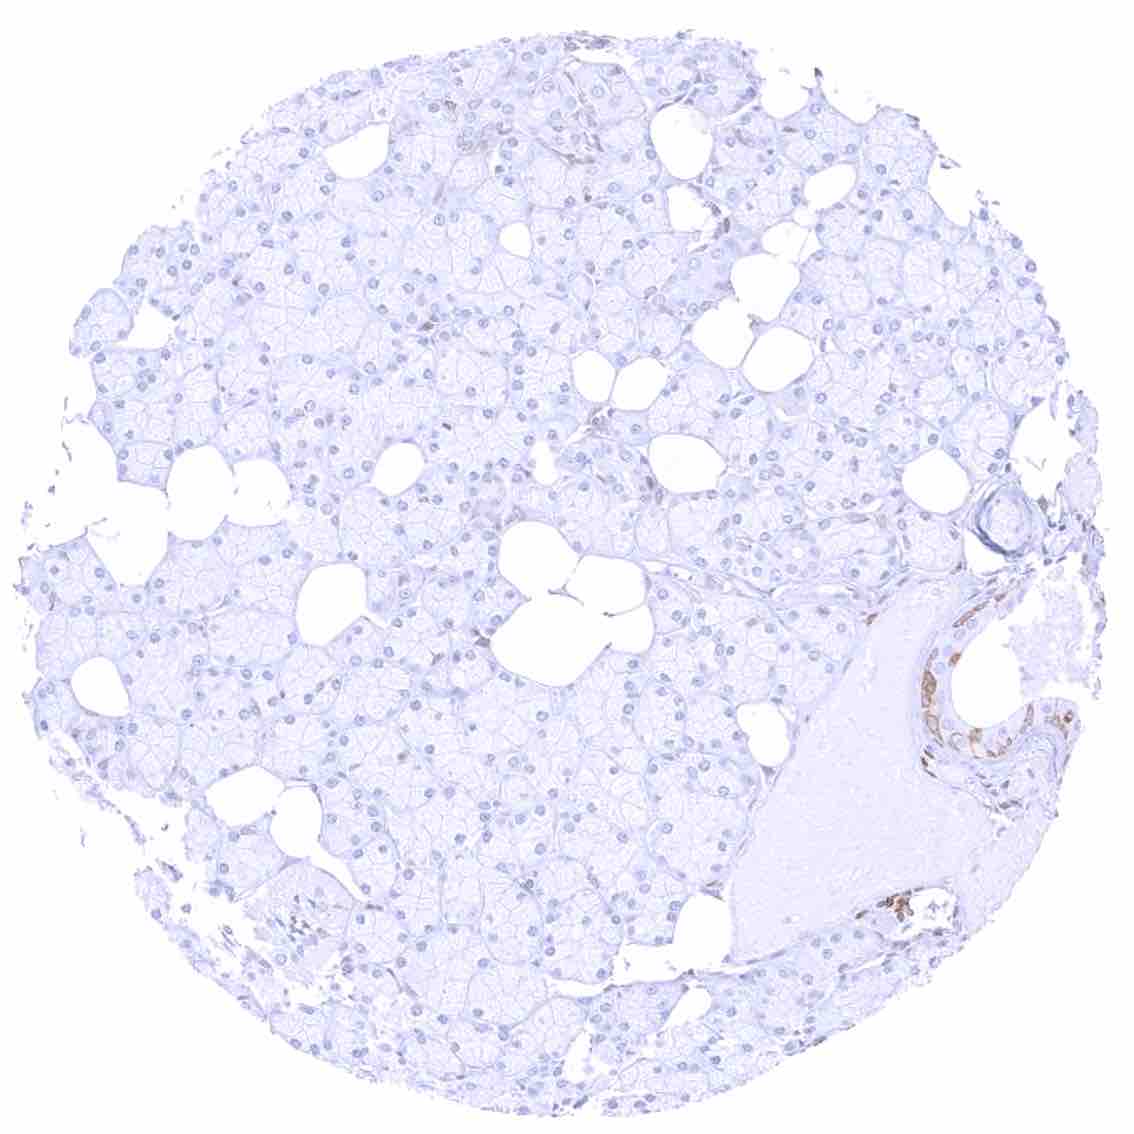

Liver